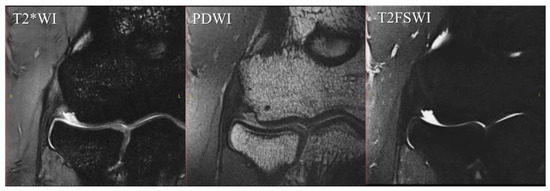

| Sequence | T2*WI | PDWI | T2FSWI |

|---|---|---|---|

| Voxel size | 0.2 × 0.2 × 1.5 | 0.2 × 0.2 × 1.5 | 0.2 × 0.2 × 1.5 |

| Matrix | 160 × 320 | 240 × 320 | 256 × 256 |

| FOV | 60 mm | 60 mm | 60 mm |

| Base resolution | 320 | 320 | 256 |

| Phase resolution | 50% | 50% | 50% |

| Slice thickness | 1.5 mm | 1.5 mm | 1.5 mm |

| TR | 553.0 ms | 553.0 ms | 3000.0 ms |

| TE | 24 ms | 24 ms | 94 ms |

| Bandwidth | 180 Hz/Px | 180 Hz/Px | 145 Hz/Px |

| Flip angle | 30 | 170 | 122 |